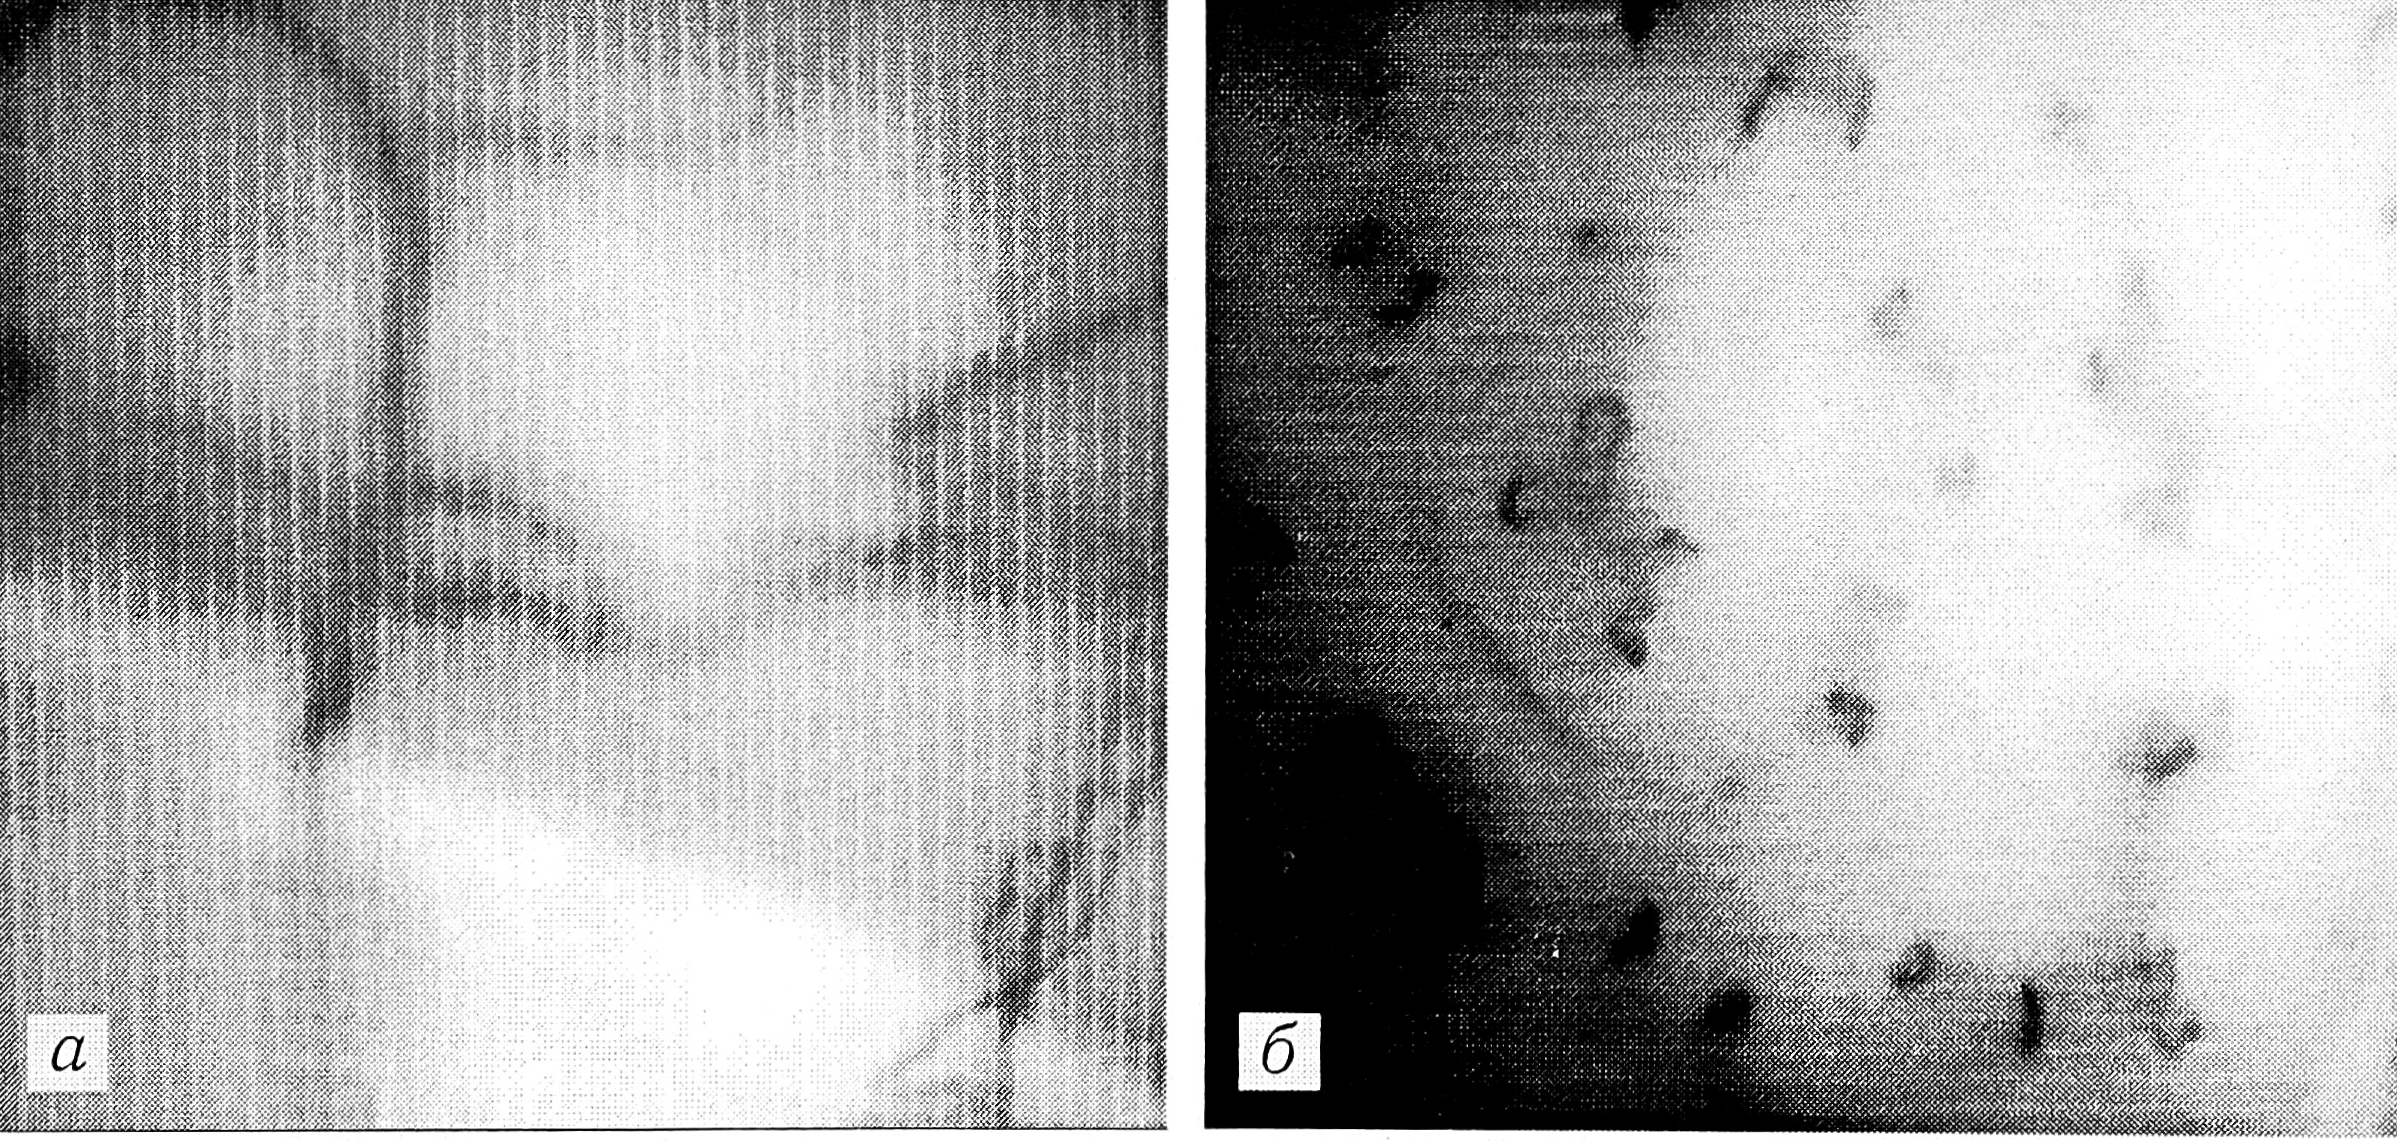

Рис. 4. Капиллярограммы (поле зрения 1 мм2) больной 65 лет с травматической микроангиопатией голени.

а — до лечения: нарушение структуры капиллярного русла кожи (резкое уменьшение функционирующих капилляров, сброс крови по шунтам); б — после курса лазеротерапии: восстановление структуры капиллярного русла.